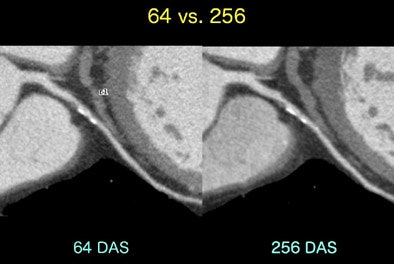

![]() |

| CT coronary angiography: 64-slice versus 256-slice. |